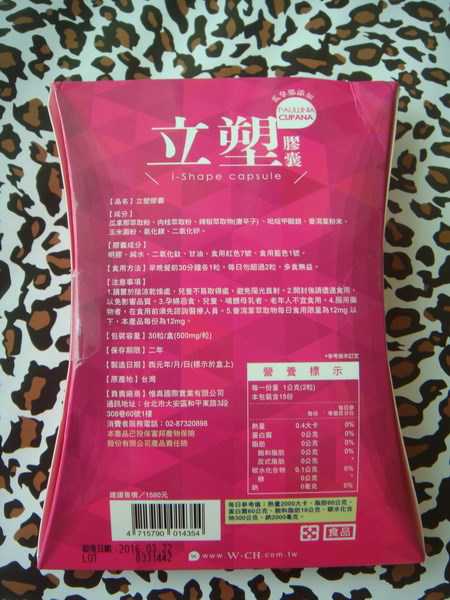

Supercut塑魔纖立塑膠囊的成分有:瓜拿那萃取粉、肉桂萃取粉、辣椒萃取物(唐辛子)、吡啶甲酸鉻、番瀉葉粉末、玉米澱粉、氧化鎂、二氧化矽。

之前上過相關課程,成分表是依照每項成分的多寡來排列順序,排在最前面的就是產品的主要成分!

食用方式:早晚餐前30分鐘各1粒,每日不超過2粒。(多食無益)

番瀉葉萃取物每日食用限量為12mg以下,